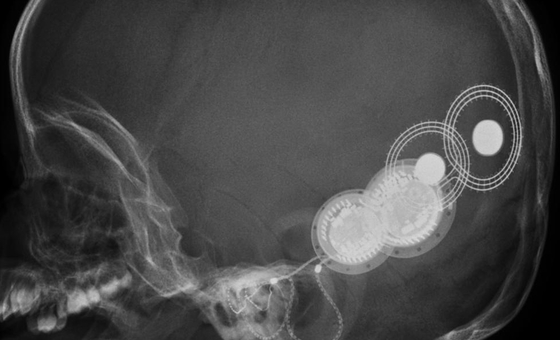

Te ofrecemos un gran número de publicaciones de profesionales médicos, que recogen desde estudios clínicos a pacientes hasta monografías exhaustivas sobre los principales temas de interés especialmente en el campo de la ORL.

Aplicación está dirigida específicamente para Otorrinolaringólogos y otros profesionales del sector, residentes y especialistas. Con ella, podrá obtener toda la información sobre las enfermedades otorinolaringológicas de cada especialidad y sus síntomas.